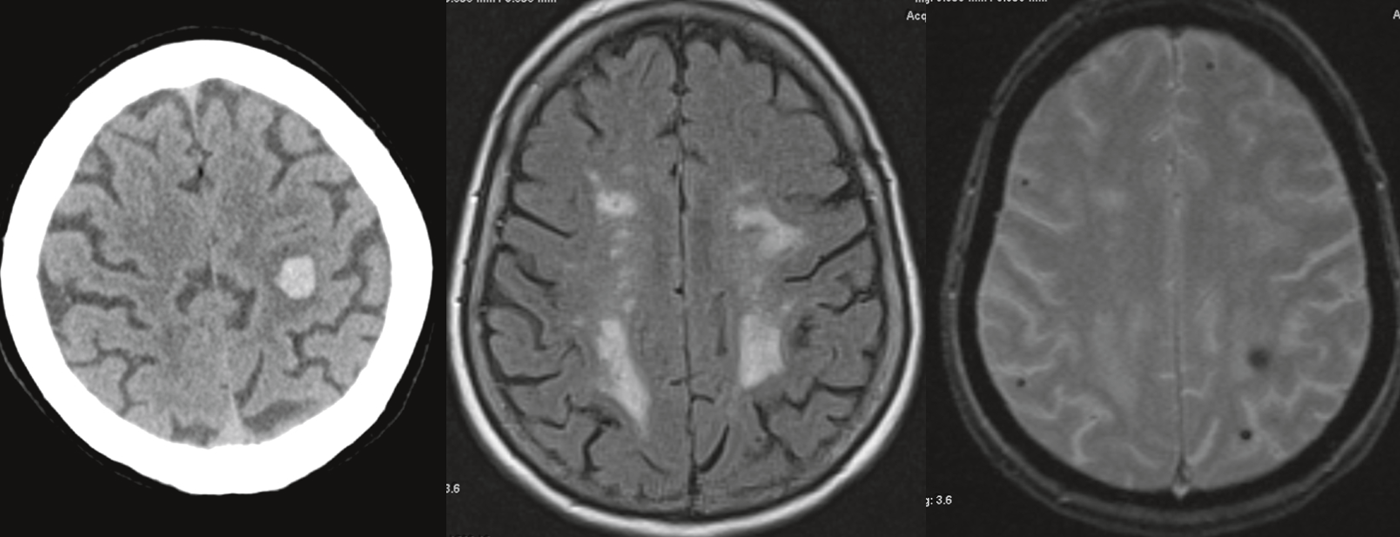

Die vaskuläre Demenz (VaD) stellt nach der Alzheimer-Demenz die zweithäufigste Demenzursache und somit die häufigste nicht-neurodegenerative Demenzform dar. Sie stellt keine ­singuläre Erkrankung dar. Klinisch von besonderer Bedeutung ist die oftmals mit einem Bluthochdruck assoziierte zerebrale ­Mikroangiopathie, welche zu einer subkortikalen ischämischen vaskulären ­Demenz (SIVD) führen kann. Diese ist die wohl am besten charakterisierte Form der VaD und ist weniger durch Gedächtnis­störungen als durch Störungen der Exekutivfunktionen und der Verarbeitungsgeschwindigkeit gekennzeichnet. Die Diagnostik basiert insbesondere auf anamnestischen, klinischen und bildgebenden Untersuchungen. ­Sie sollte in jedem Fall frühzeitig erfolgen.